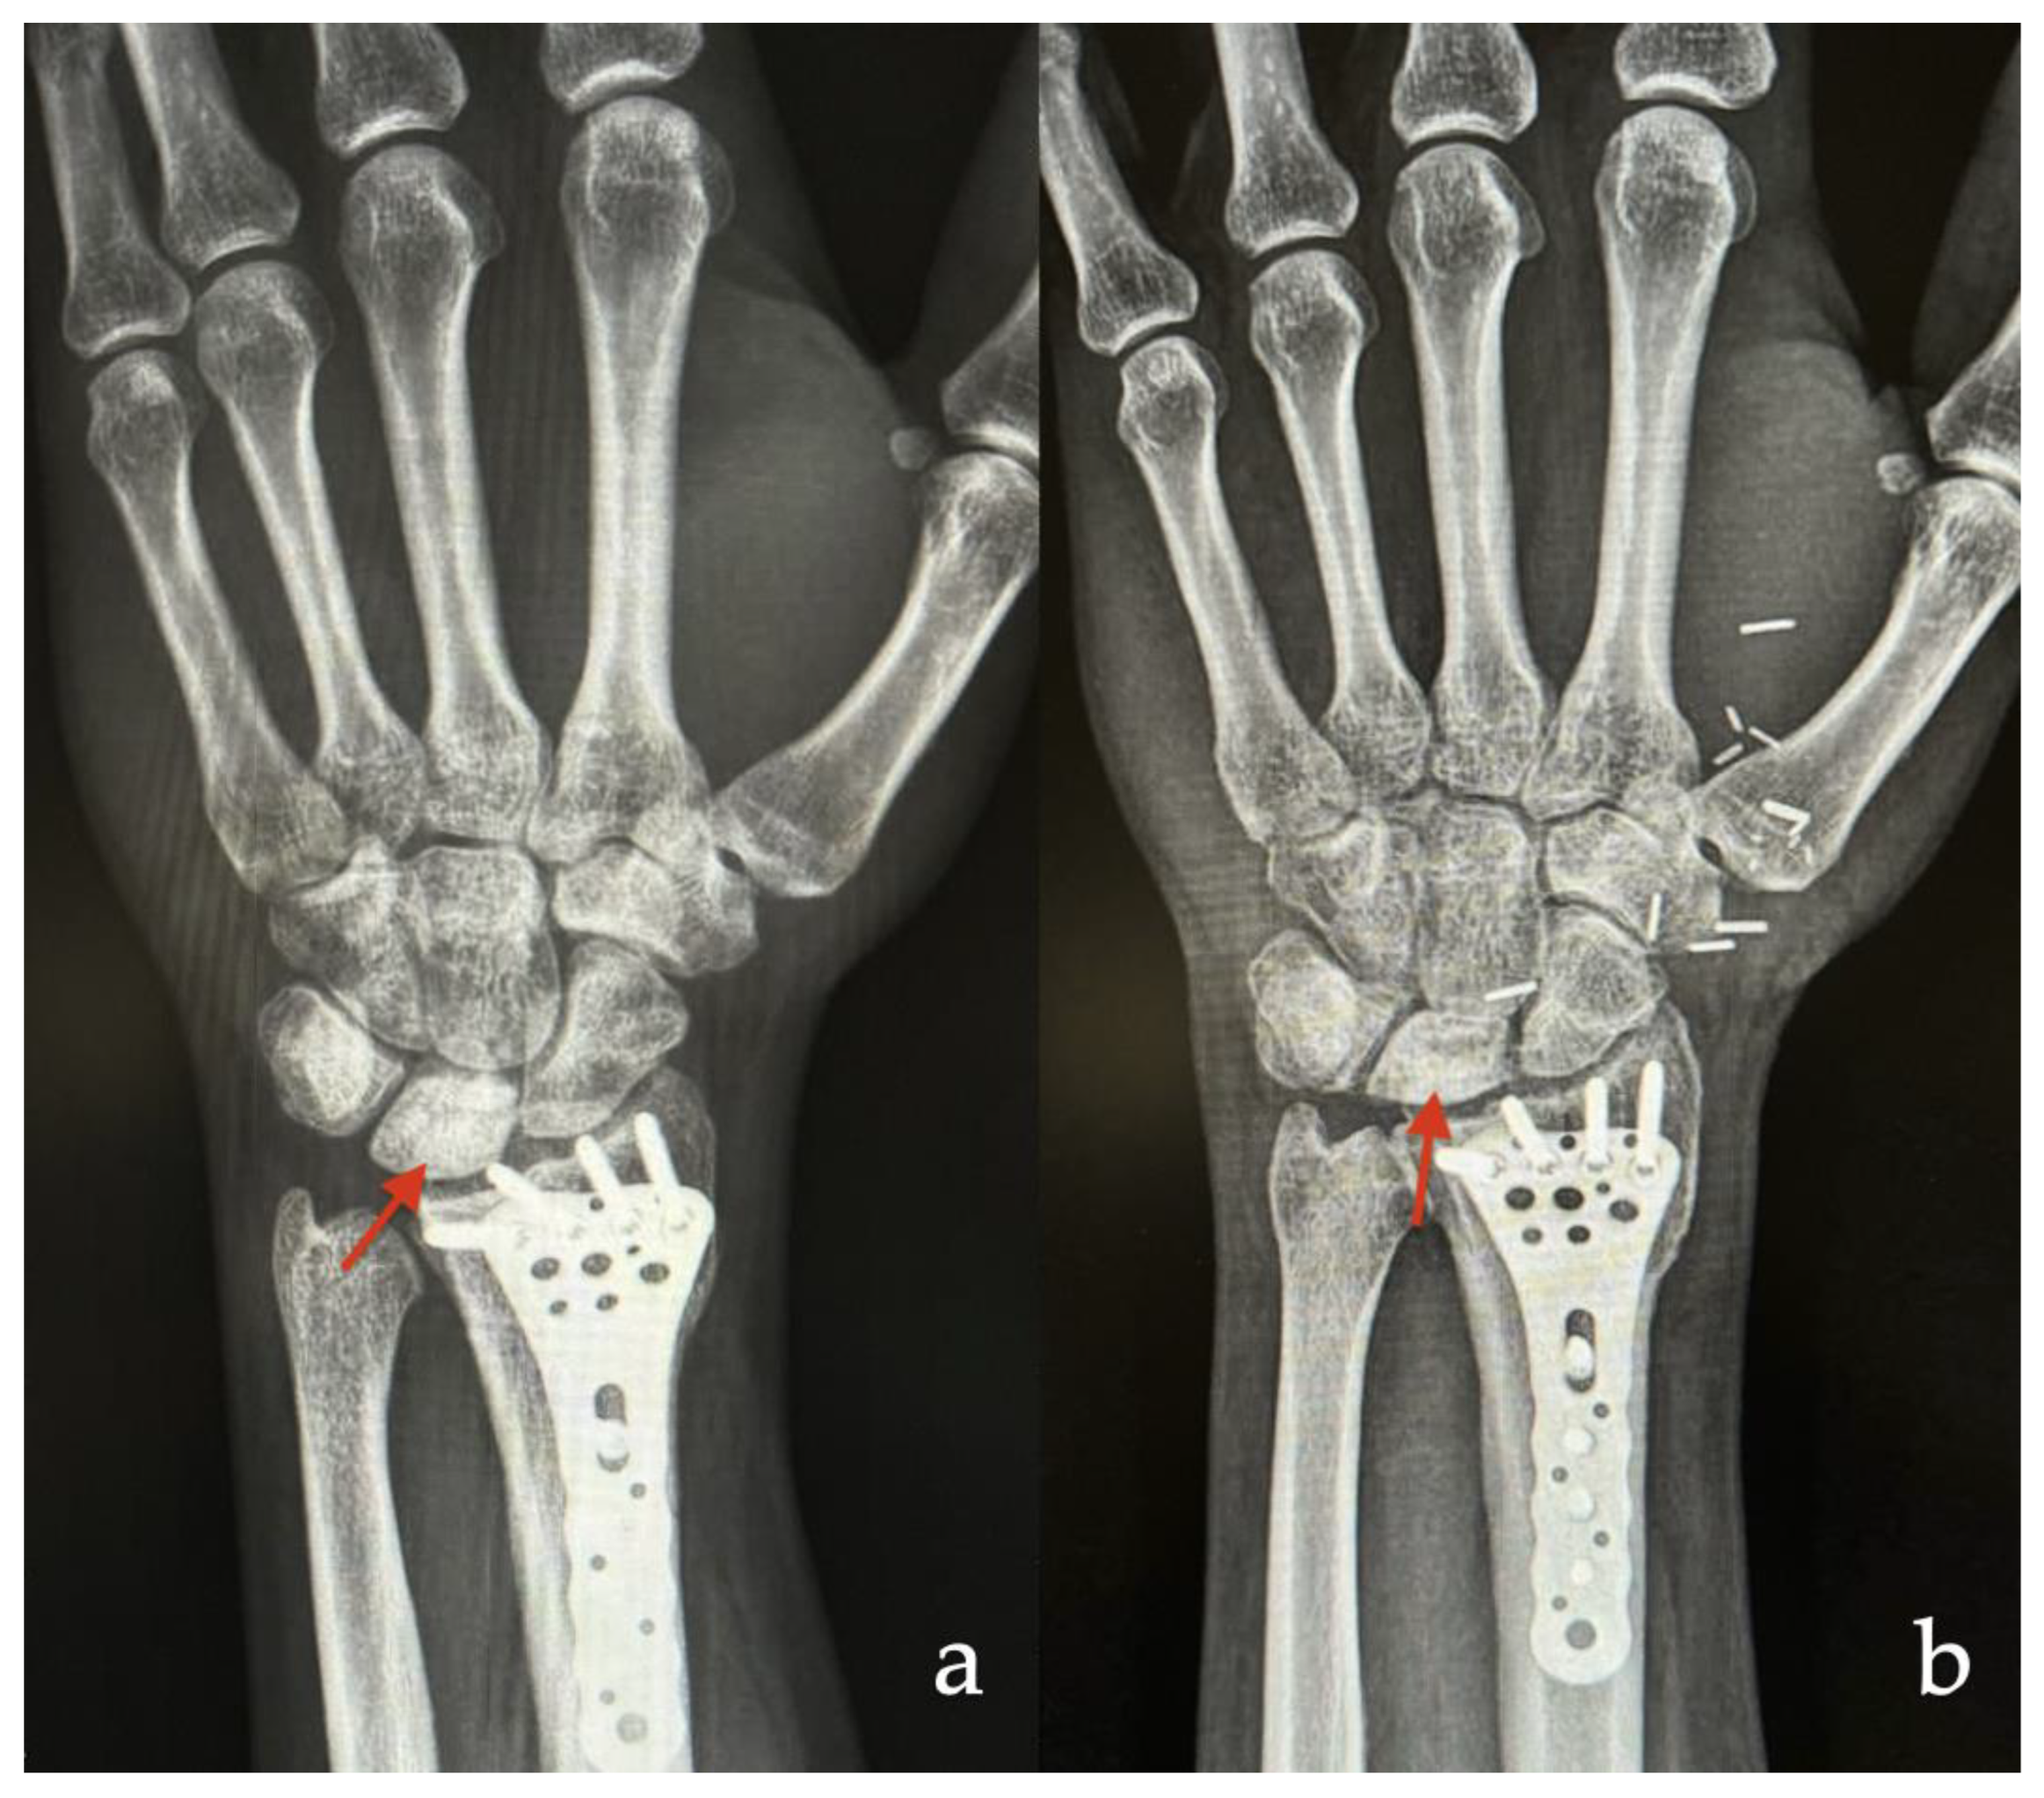

3.1.1. Case 1

| 1 | 38 | M | Scaphoid | Nonunion (avascular necrosis) | Osteochondral | 24 |

| 2 | 19 | M | Scaphoid | Nonunion (avascular necrosis) | Osteochondral | 12 |